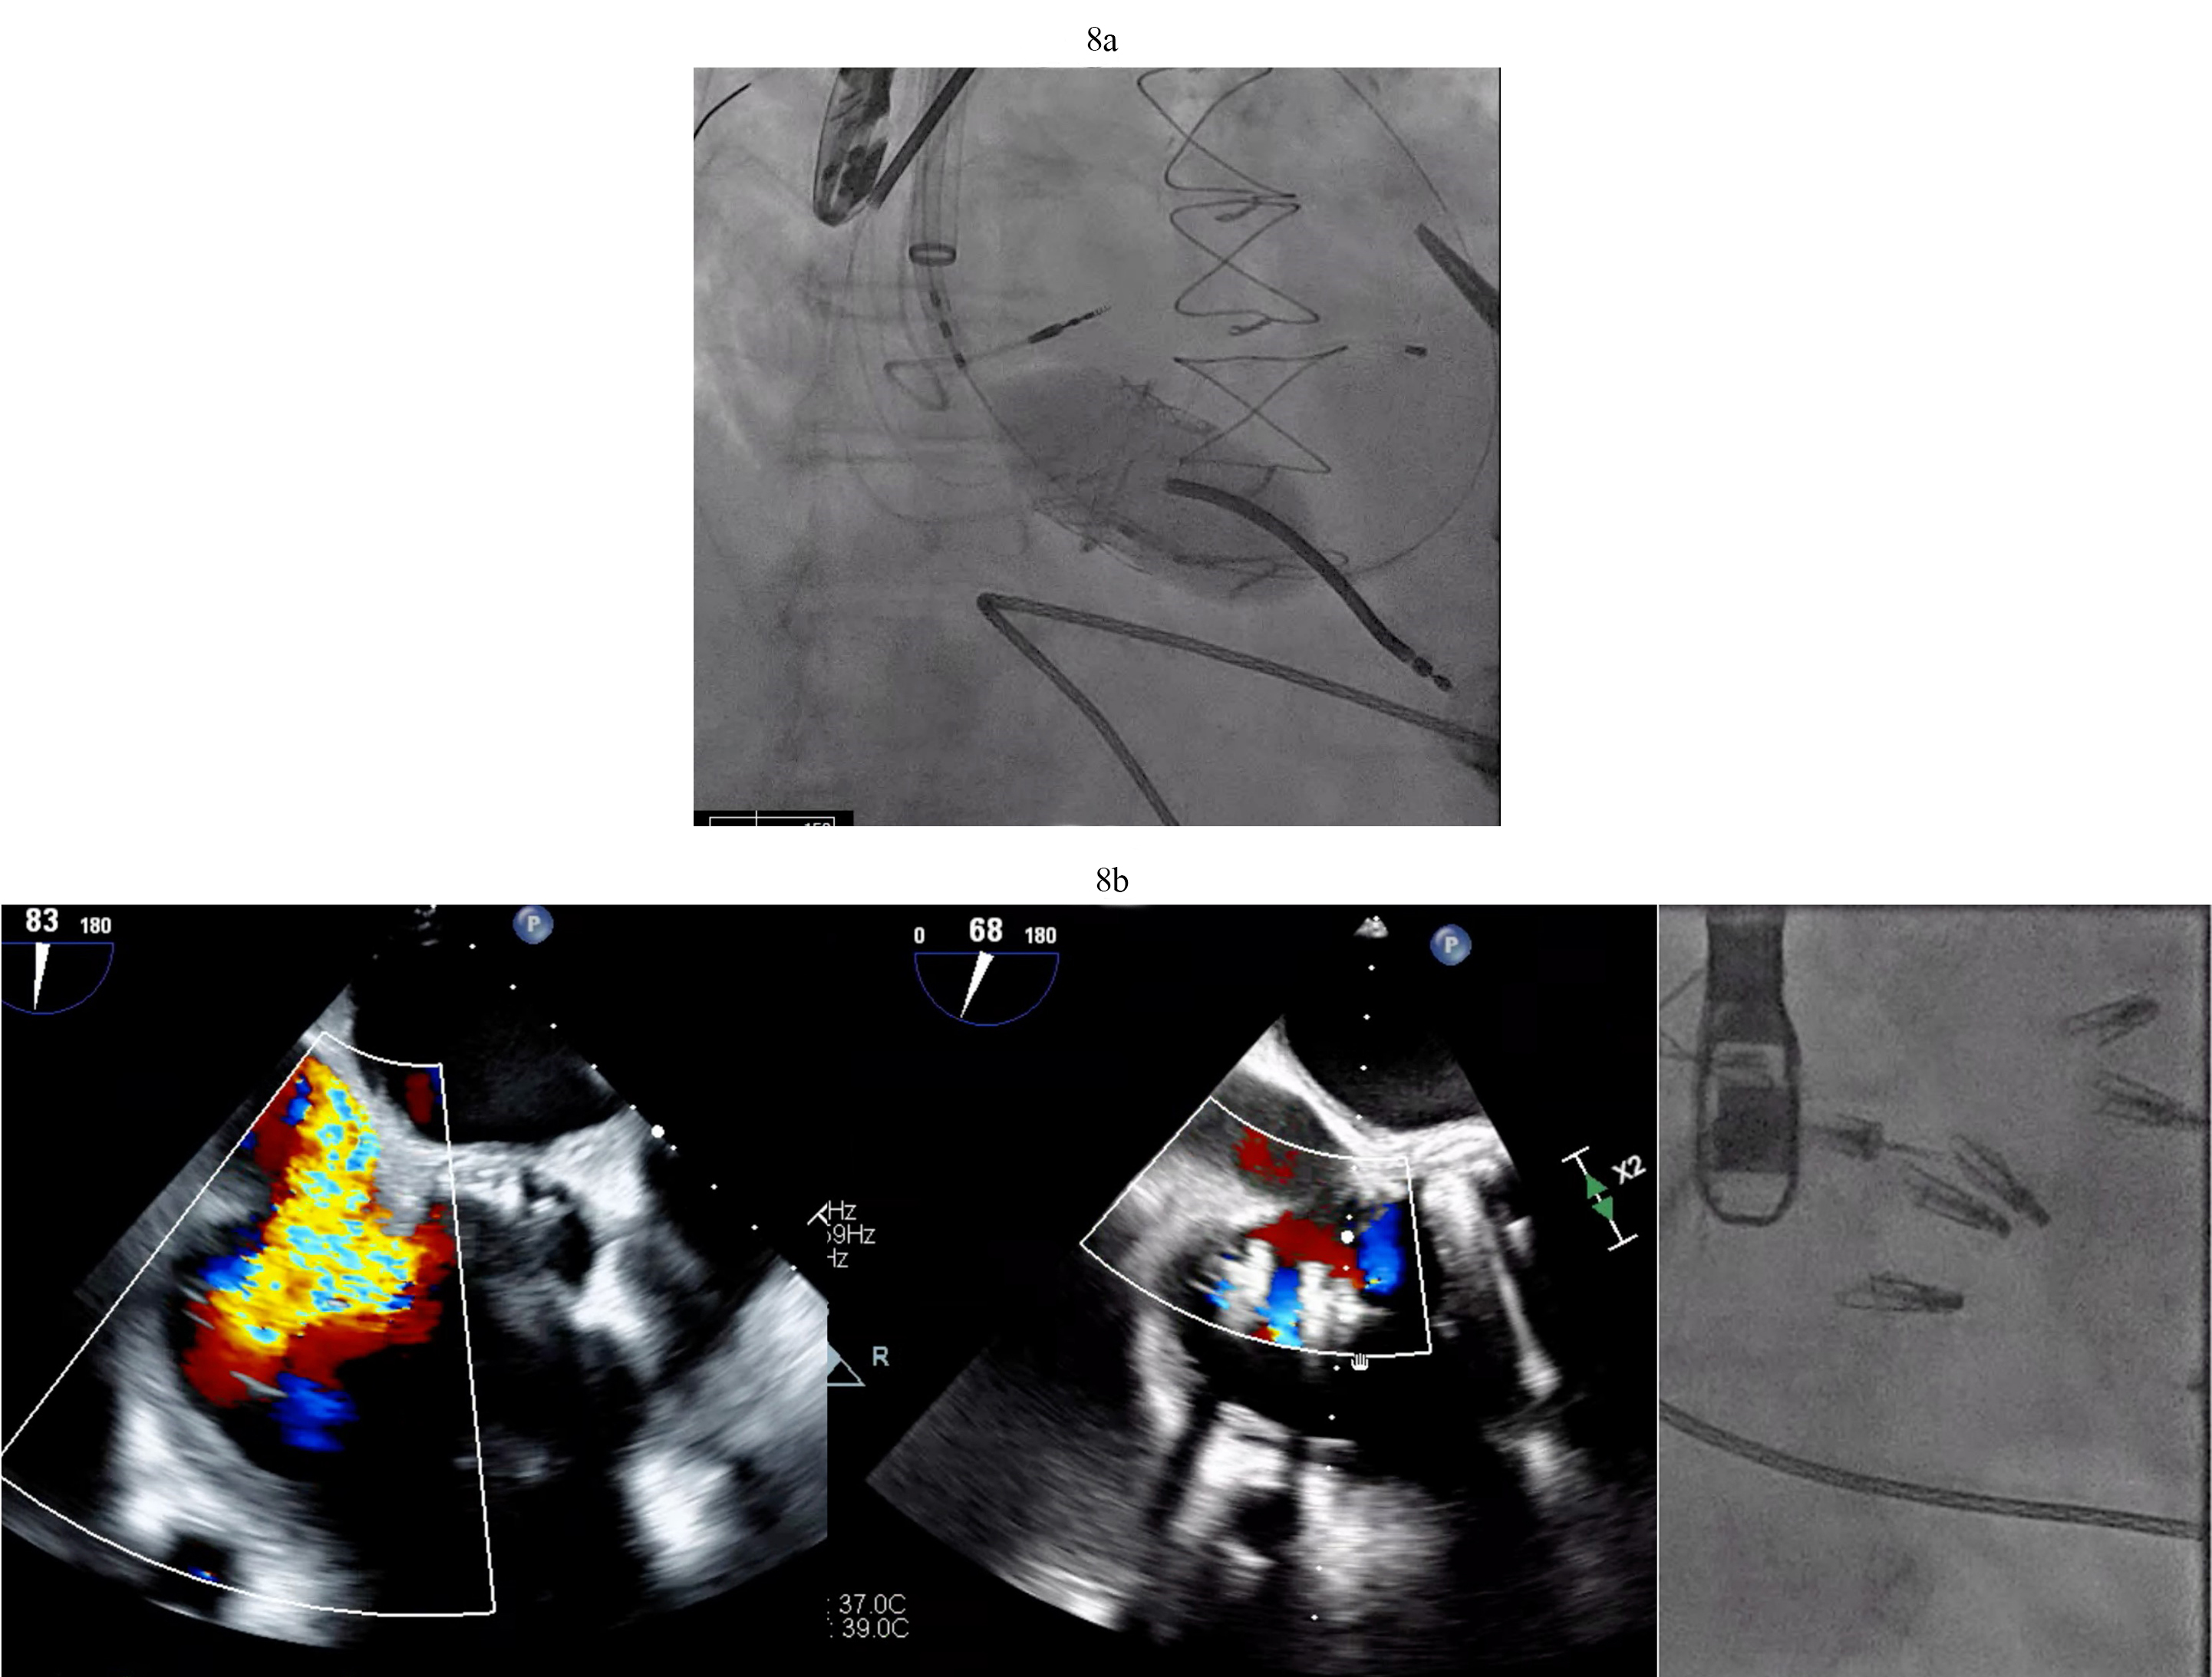

The determination of what is significant is driven by two factors. The size of the defect certainly plays a role but more importantly one needs to consider that RV dysfunction and elevated right -sided filling pressures may occur post LVAD in the immediate post operative state. PFOs can become very problematic in circumstances of significant RV failure post LVAD. As right atrial pressures rises, right to left shunting increases (Fig. 9a). This shunting can result in hypoxemia that worsens pulmonary vascular resistance and leads to worsening right ventricular function with further increases in right atrial pressures. This vicious cycle can quickly derail a stable post-operative course. Percutaneous PFO closure can effectively stop right to left shunting and ameliorate symptoms (Fig. 9b). In situations where right ventricular hemodynamics are tenuous, compromising LVAD preload and flows and jeopardizing end organ function, RVADs may be required to stabilize the patient’s condition prior to PFO closure (Fig. 9c).

Fig. 9. PFO closure post LVAD. (a) Large right to left shunt in a patient with PFO and RV failure. (b) Amplatzer closure of PFO in LVAD patient. (c) Successful closure of PFO with Gore 32 mm ASD occluder. Patient on RVAD support due to worsening RV failure in the settting of hypoxemia. RV, right ventricular; RVAD, right ventricular assist device.